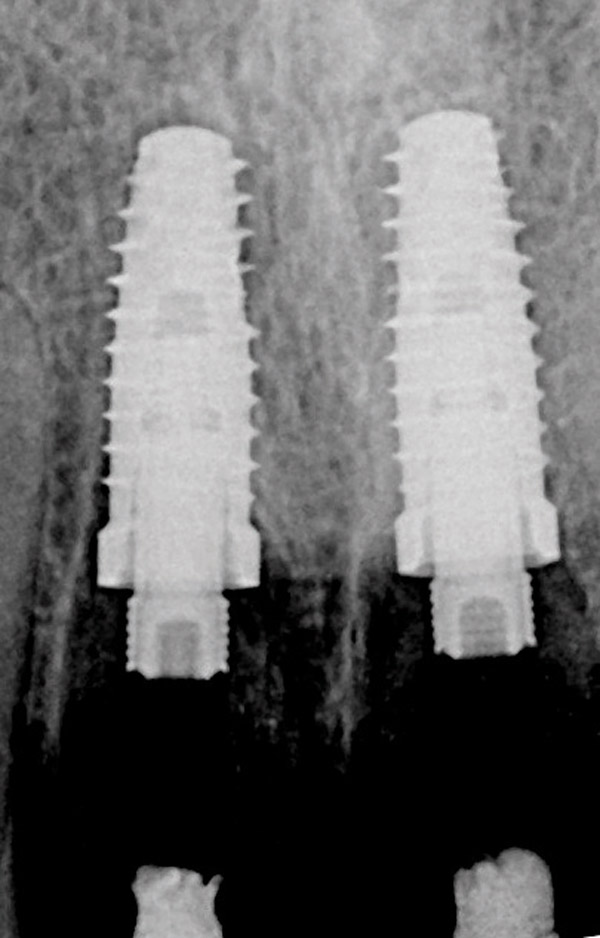

Figure 3  Periapical radiograph of implants in the Nos. 8 and 9 sites 3 years after placement. A bony peak was still present between the implants due to successful guided bone regeneration and favorable fixture spacing.

Figure 3

Figure 11  Periapical radiograph at the time of provisionalization. Note the wide peak of bone between implants Nos. 8 and 9.

Figure 11